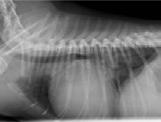

Ecocardiográficamente se observó una dilatación severa del atrio izquierdo (AI) (ratio aorta/atrio izquierdo4 de 3,88; diámetro normalizado del atrio izquierdo5 de 26,91) y dilatación del ventrículo izquierdo (diá-

11

metro interno del ventrículo izquierdo normalizado en diástole6 de 2,28) secundarios a un engrosamiento, fallo de coaptación y prolapso de las valvas de la válvula mitral, determinando una regurgitación mitrálica posterior grave. Se realizó radiología torácica para valorar la presencia de edema pulmonar, observando un patrón intersticial-alveolar severo en el área perihiliar y en los lóbulos caudales pulmonares, compatible con la presencia de edema pulmonar de origen cardiogénico. Tras la realización de la radiografía torácica, se diagnosticó ECDVM en estadio C7 agudo, con una puntuación ecocardiográfica de la insuficiencia mitral (MINE)8 de 12. No se observó derrame pericárdico durante la realización del examen (Figs. 1 y 2).

Figura 1. Corte paraesternal derecho 4 cámaras, previo a la rotura del atrio izquierdo. VI: ventrículo izquierdo; VD: ventrículo derecho; AI: atrio izquierdo; AD: atrio derecho. Figura 2. Corte paraesternal derecho transversal a la altura del atrio izquierdo y aorta, previo a la rotura del atrio izquierdo. Ao: aorta; AI: atrio izquierdo. Figura 3. Radiografía torácica latero-lateral derecha realizada en el momento que se produjo la rotura del atrio izquierdo. Figura 4. Examen TFAST tras la rotura del atrio izquierdo donde podemos observar un corte transversal del corazón a la altura de los músculos papilares de ventrículo izquierdo. Se puede observar la presencia de derrame pericárdico. VD: ventrículo derecho; VI: ventrículo izquierdo.